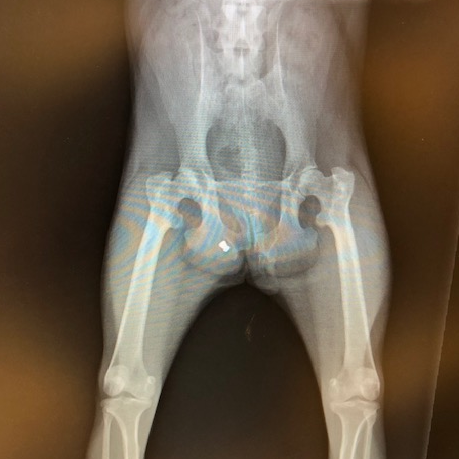

When Sasha and Kali arrived at our rescue centre, they underwent a thorough check-up by our vet team, who made a shocking discovery: a bullet, lodged in Sasha’s hindquarters.

It is not clear exactly when or how the bullet ended up there. For now, the bullet does not appear to be causing Sasha any pain. We are therefore waiting for her to recover from the stress of her rescue before we consider surgical removal.